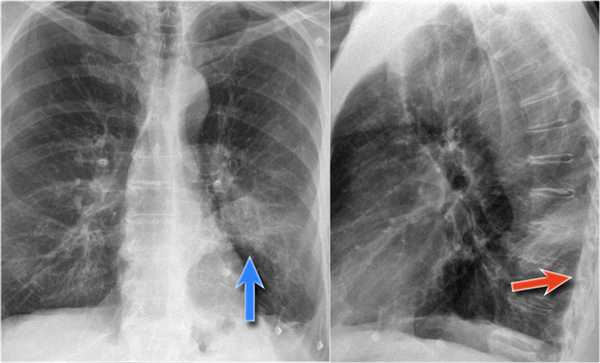

Ателектаз нижней доли правого легкого.

На нижепредставленой рентгенограмме пациента 70 лет, упавшего с лестницы, в плевральной полости определяется скопление жидкости, предположительно являющейся кровью.

Это ателектаз нижней доли правого легкого.

Обратите внимание на правую границу сердца. Правая междолевая артерия не видна потому, как она не окружена воздушной легочной тканью, а закрыта спавшейся нижней долей правого легкого.

Ниже представлены последующие рентгенограммы органов грудной полости того же пациента, на которых ателектаз разрешен.

Обратите внимание на правую междолевую артерию (красная стрелка) и границы правых отделов сердца (синяя стрелка).